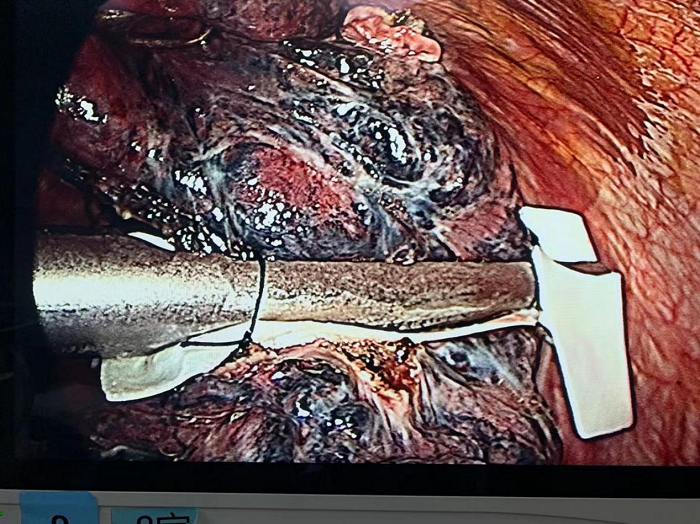

胸片檢查后考慮左側(cè)大量氣胸,入院后予行左側(cè)胸腔閉式引流術(shù),引出大量氣體。第3天復(fù)查胸部CT考慮,雙肺肺氣腫,左肺可見數(shù)個(gè)肺大皰,較大者大小約5cm10cm,患者平靜狀態(tài)下左側(cè)胸腔引流瓶可見持續(xù)有氣泡溢出,考慮左側(cè)肺大皰破裂口未閉合。起初老伯家屬要求保守治療,可是老伯左側(cè)胸管仍大量氣泡溢出,如果繼續(xù)保守治療,肺大皰破裂口愈合時(shí)間不確定,也可能長(zhǎng)時(shí)間不愈合,那胸管就不能拔除,還有加重肺部、胸腔感染的風(fēng)險(xiǎn)。綜合考慮老伯的病情和身體,胸外科團(tuán)隊(duì)充分討論后認(rèn)為,雖然麻醉及手術(shù)風(fēng)險(xiǎn)較高,還仍希望能夠從根本上解決老伯胸腔“漏氣”的情況——可嘗試為老伯行胸腔鏡微創(chuàng)手術(shù)治療,術(shù)中使用外科生物補(bǔ)片作為“墊片”,以確保肺切緣不漏氣。

完善相關(guān)術(shù)前準(zhǔn)備后,胸外科團(tuán)隊(duì)行“胸腔鏡下肺減容術(shù)”,術(shù)程順利,考慮老伯基礎(chǔ)疾病多,心肺功能差,予轉(zhuǎn)ICU監(jiān)護(hù)治療,拔除氣管插管后轉(zhuǎn)回普通病房。

外科肺減容術(shù)(Lung volume reduction surgery)是治療重度肺氣腫的有效方法。該法由Brantigan于1959年首先提出,1994年Cooper教授對(duì)LVRS的早期理論及技術(shù)作了進(jìn)一步的改進(jìn)。隨著微創(chuàng)手術(shù)的進(jìn)步,由傳統(tǒng)開胸手術(shù)轉(zhuǎn)至胸腔鏡微創(chuàng)手術(shù),術(shù)中使用直線切割縫合器加快肺組織的切割和縫合速度,應(yīng)用牛心包墊片加固切緣減少肺漏氣,提高手術(shù)安全性及治療效果。